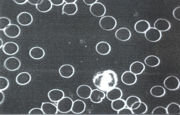

Eine wichtige Diagnosemöglichkeit ist die Beurteilung der roten Blutkörperchen, der Erythrozyten. Sie sorgen für den Abtransport der Zellabbauprodukte und bringen gleichzeitig aus den Lungen den notwendigen Sauerstoff zu jeder einzelnen Zelle.

Eine „Geldrollenbildung“, das Zusammenballen mehrerer Erys, ist ein erster Hinweis auf Durchblutungsstörungen. Kalte Hände und Füße, später Krampfadern, Hämorrhoiden, Thrombosen bis zu Herz-/Hirninfarkt sind mögliche Folgen. Es kann aber auch ein Hinweis auf eine poröse Darmschleimhaut sein, das „leaky gut syndrom“.